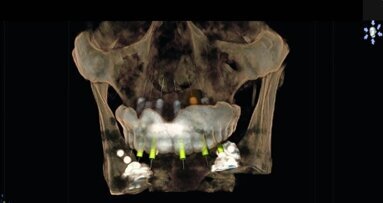

Sirona’s GALILEOS scan travels around the patients’ head in a single revolution that takes 14 seconds to complete the capture of the maxillofacial anatomy and a full volume of data is reconstructed and becomes available to assess within minutes. My patient and I reviewed the 3-D images together on a large computer monitor in my conference room. I was able to place three virtual implants into the residual bone avoiding the IAN, mental foramen and lingual concavity. Patient could clearly visualise this procedure being performed in his jaw. In this case the bone appeared adequate to receive three endosseous implants that could be restored with a 4-unit fixed bridge (Figs. 4–7). So to recap, this patient was reluctant to be treated with conventional flapped implant surgery and declined additional bone grafting to improve any bone volume, but was a candidate for flapless or minimally flapped guided implant surgery which gave him the confidence to accept treatment based upon our initial consultation and treatment plan which was developed during this visit. This first step is essential to gain the patient’s trust and gain acceptance to the treatment plan at his initial visit as he would not return to us if he wasn’t convinced that I could perform his treatment as I described and under local anesthesia and without further bone grafting.

In preparation for guided implant surgery it is necessary to fabricate a computer generated surgical guide based upon the restoratively driven prosthetic design that is developed to return the patients dentition to form and function. I am able to create a plan based on the available bone and the future positions of the prosthetics. Study models were obtained and duplicated so that the laboratory could create a wax up of the four missing teeth in their correct occlusion. I duplicated the wax up and made a .060 omnivac suck down which represented the crowns in their proposed positions. Within this omnivac I inserted radiopaque acrylic in the area of teeth #28–31 and attached a SICAT proprietary biteplate with acrylic, which became the radiographic scan appliance worn while the CBCT scan was taken. It is necessary to scan the patient with a Sirona proprietary biteplate secured over the patients’ dentition so that SICAT can merge the data sets from the 3-D imaging and the patients dentition. I can then place the virtual implants in their best positions relative to the proposed crowns and bone volume present.

Following the scan, a definitive implant plan is created that will mimic the actual dimensions of the Nobel Active implants to be placed at the time of surgery. Sirona provides its clients with a vast library from which to choose whatever implant manufacturer you prefer to work with. This ensures that my plan will be executed properly with the osteotomies performed to my specifications at the surgical visit. Submillimeter accuracy from plan to actual is a clear benefit derived from enhanced imaging and advance treatment planning. I sent the CBCT data and a cast of the patient’s dentition that SICAT optically scans and integrates with the implant plan that I created and used to mill out and fabricate the surgical guide. It takes two weeks to receive an accurately fitting Classic SICAT surgical guide back in my office which would be used during patient’s guided implant surgery.

The Sirona system is the only complete system that doesn’t require a third party software or manufacturer to create their surgical guides. Figures 8–10 show the virtual implants placed into the area of tooth #28, 30 and 31. Please note the measurement taken buccal-lingually at the #28 site and the anatomical limitations dictated by the lingual concavities present at the #30 and #31 sites. Some compromises were necessary to ensure safe, predictable and long lasting success of our implants. They were dictated by the anatomical bone limitations present and the patients’ refusal for any additional bone grafting.